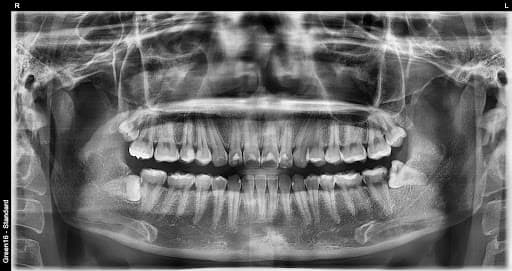

Yotgan aql tishi

Yon tomonga qarab o'sadi va qo'shni tishni bosishi mumkin

Yallig'lanish paydo bo'lishi

E'tiborsiz qoldirilgan aql tishi tufayli milk shishib, yallig'lanishi mumkin

Murakkab ko'milgan aql tishi - milkda chuqur yashiringan bo'lsa ham OK

Asabga yaqin aql tishi - asab shikastlanishi xavotiri yo'q xavfsiz olish

Gorizontal ko'milgan aql tishi - yonga yotgan murakkab hollarni ham bajara olamiz